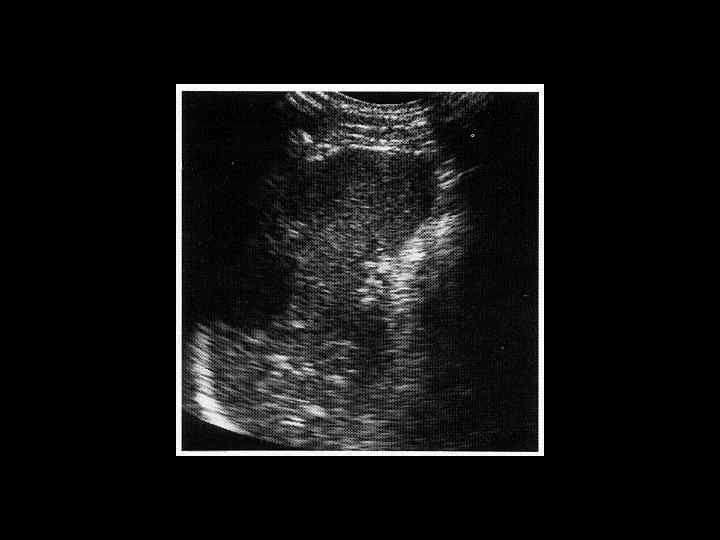

АКТУАЛЬНЫЕ ВОПРОСЫ РЕНТГЕНОЛОГИИ ЛУЧЕВАЯ ДИАГНОСТИКА ЗАБОЛЕВАНИЙ СЕЛЕЗЕНКИ Методы лучевого исследования: 1. Обзорная рентгенография 2. Ультразвуковое исследование 3. Компьютерная рентгеновская томография 4. Магнитно-резонансная томография 5. Радионуклидное исследование

АКТУАЛЬНЫЕ ВОПРОСЫ РЕНТГЕНОЛОГИИ ЛУЧЕВАЯ ДИАГНОСТИКА ЗАБОЛЕВАНИЙ СЕЛЕЗЕНКИ Кисты и абсцессы селезенки

АКТУАЛЬНЫЕ ВОПРОСЫ РЕНТГЕНОЛОГИИ ЛУЧЕВАЯ ДИАГНОСТИКА ЗАБОЛЕВАНИЙ СЕЛЕЗЕНКИ Травма и инфаркт селезенки

АКТУАЛЬНЫЕ ВОПРОСЫ РЕНТГЕНОЛОГИИ ЛУЧЕВАЯ ДИАГНОСТИКА ЗАБОЛЕВАНИЙ СЕЛЕЗЕНКИ Опухолевое поражение селезенки